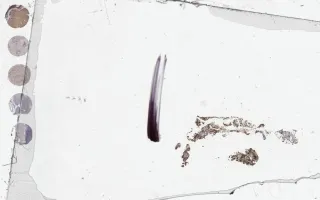

4) Acute megakaryoblastic leukemia - excluded because the blasts in the biopsy are negative for Factor VIII and CD61. You should have noticed the interstitial infiltrate of blasts. You must look at the blasts to see if they express these markers not the mature megakaryocytes which would be expected to express these markers. Also, don't overcall the sticky platelets which will also pick up these markers.

This slide shows Factor VIII stain of bone marrow biopsy. See related content for peripheral blook, bone marrow aspirate, and H&E and IHC stains of bone marrow biopsies.